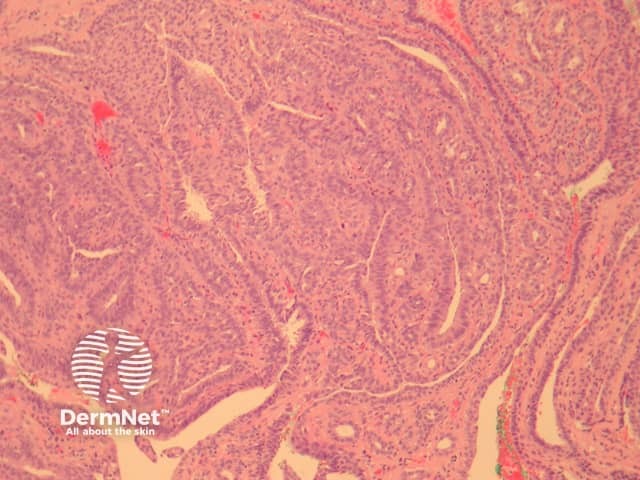

In erosive papillomatosis of the nipple, sections show a papillary epithelial proliferation which connects with the overlying epidermis (figure 1). The lesion consists of fibrovascular cores lined by bland cells (figure 2). The cells are usually at least 2 layers thick and consist of a myoepithelial layer and an epithelial layer which may exhibit apocrine differentiation (figure 3)

Figure 2